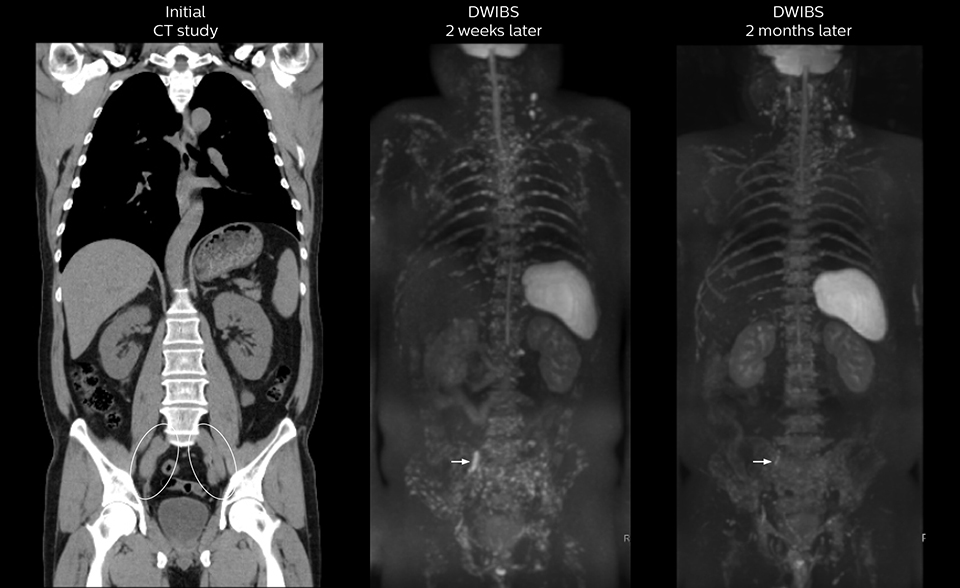

After implementing the improved whole body protocol, the radiology team initially did not see a large increase in referrals, although Dr. Nobusawa saw clinical cases where the DWIBS images provided him valuable information for diagnosis. This is why Dr. Nobusawa and Mr. Naka started to actively educate referring physicians about the value of whole body DWIBS. They organized several presentations for physicians in the hospital, where they explained how DWIBS can be of value in oncology patients. The information it provides can be useful for physicians when staging cancer, as well as when determining or adjusting treatment strategy. Mr. Naka remembers some cases where DWIBS provided remarkable information. “In one example, DWIBS visualized bone lesions that could not be seen on PET or SPECT. In another case we had found a bone lesion when a normal L-spine scan for narrowing of the disk space was done. One extra DWIBS scan (2 stations, 8 minutes) demonstrated a lesion that later was confirmed to be the primary region of cancer.”

In certain cases, radiologists now choose DWIBS to make diagnoses that used to depend on nuclear medicine studies. “We don’t have SPECT or PET in our hospital, so for instance for visualizing metastasis and monitoring the effect of treatments such as chemotherapy or radiotherapy, we used to refer patients outside the hospital. Now, these patients are sent to MRI for our whole body protocol with DWIBS,” Mr. Naka says.